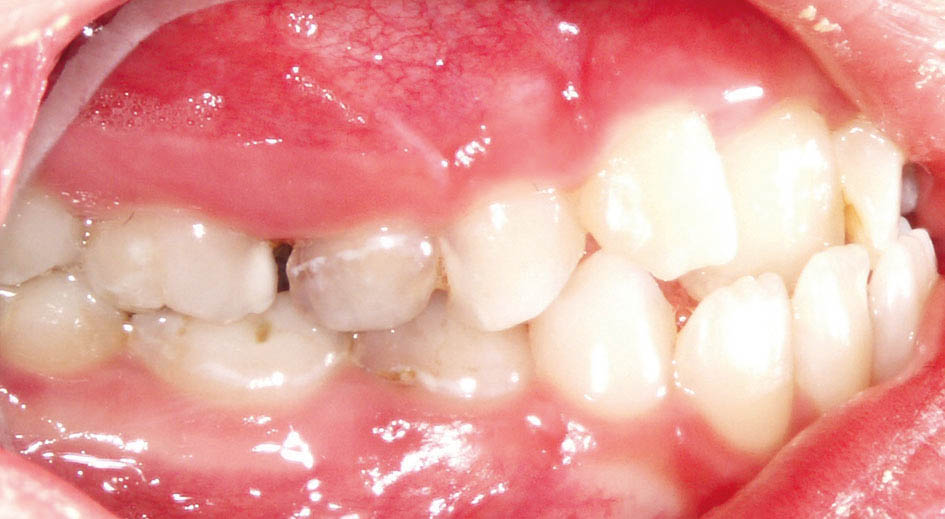

بعد از آن بایستی صبر کنیم تا تمام دندانهای دائمی رویش یابند (شکل 43-5 الی 45-5). با چنین کار سادهای شما از کلاسIII شدن، تنگی ماگزیلا، انحراف طرفی مندیبل (بخاطر کراس خلفی یک طرفه) و انحراف قدامی مندیبل (بخاطر کراس قدامی دندانها) جلوگیری میکنید. اگر قادر به اینگونه درمانها نباشید چنین بیماری دارای عوارض بسیاری میشود و در بزرگسالی نیاز به چندین عمل جراحی خواهد داشت و معمولاً نتایج درمانهای جراحی به زیبایی چنین کارهای ساده ارتودنسی (شکل 46-5) نمیشوند.

برای نگهدارنده بعد از RPE یا پالاتال بار یا پلاک Hawley میدهیم و برای نگهدانده درمان کراس قدامی اگر دیپ بایت باشد چیزی نمیدهیم و اگر دیپ بایت نباشد یک سیم twisted به بیمار میدهیم. در این بیمار یک پالاتال بار و یک سیم twisted قرار دادیم.

شکل 43-5: تکمیل رویش دندانهای قدامی با اکلوژن کلاسI در سمت راست

شکل 44-5: اکلوژن کلاسI در سمت چپ

شکل 45-5: میدلاین صحیح بیمار فوق پس از درمان